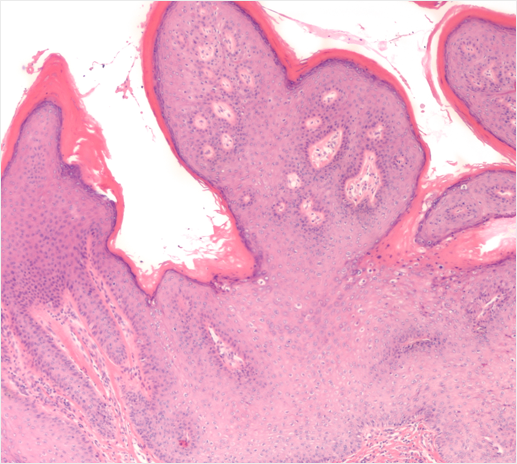

콘딜로마

Condyloma

인유두종 바이러스(HPV)가 원인으로

성기나 항문 주변에 닭벼슬 모양으로 번지는 사마귀

약물 치료나 레이져, 혹은 고주파 치료로 쉽게 치료가 되는 반면

근본적인 원인 치료가 안되기 때문에 재발이 잘 됩니다.

최근에는 HPV 백신 접종을 통해 예방이 어느 정도 가능합니다.

콘딜로마가 생겼다면 즉시 치료를 받아야 하는데 자궁 경부에 고위험군

HPV 감염이 있을 경우는 자궁경부암을 일으킬 수도 있으므로 반드시 HPV검사 및

자궁 경부 세포진 검사를 받고 향후에도 정기적인 산부인과 검진

을 받아야 합니다.